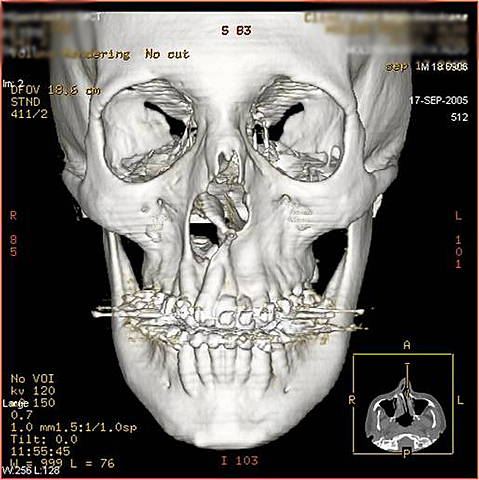

• Anatomia humana

Anatomia humana

Mansfield y A.A. Maudsley en 1977 publicaron la primera imagen

seccional de una región de la anatomía humana, un

dedo. Doble hélice del DNA.

Los hallazgos de Mansfield y Lauterbur y del

mismo Damadian aceleraron el desarrollo de la técnica.

En 1977, W. Hinshaw et al. publicaron imágenes de

RM de la muñeca, R. Damadian logró reconstruir la

imagen del tórax y P. Mansfield desarrolló las secuencias

EPI. R. C. Hawkes y Moore et al en 1980 obtuvieron

las primeras imágenes de la cabeza